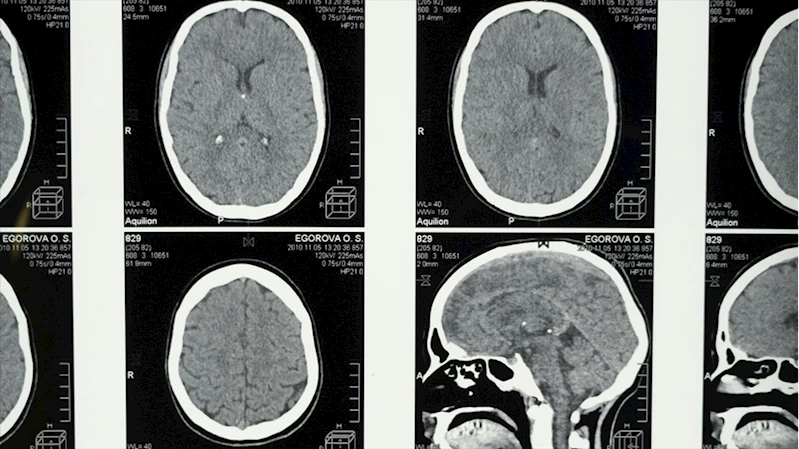

İSTANBUL (AA) - Science Daily'nin haberine göre araştırmacılar, yaş ortalaması 70 olan ve yarısına daha önceden Alzheimer teşhisi konulmuş 128 kişiyi klinikte uyutarak gözlemledi.

Araştırmacılar, deneklerin beyin dalgası aktivitelerini, kalp atış hızlarını ve solunum düzenlerini ölçtü.

Rüya görmeye başlanan REM evresine geçiş sürelerine göre denekleri 2 gruba ayıran araştırmacılar, uykuya daldıktan sonra ortalama 98 dakikadan kısa sürede REM evresine ulaşanlar "erken", yaklaşık 193 dakikadan daha uzun sürede geçenler ise "geç" grup olarak sınıflandırdı.

Çalışma sonucunda, uykunun REM evresine "geç" ulaşan kişilere, daha önce Alzheimer hastalığı tanısı konmuş olma ihtimalinin daha yüksek olduğu tespit edildi.

Uyku apnesi gibi rahatsızlıkların tedavi edilmesi ve aşırı alkol tüketiminden uzak durulması çağrısı yapan araştırmacılar, uykunun REM aşamasına önem gösterilmesi gerektiğini vurguladı.

Araştırmanın bulguları "Alzheimer Derneği" dergisinde yayımlandı.